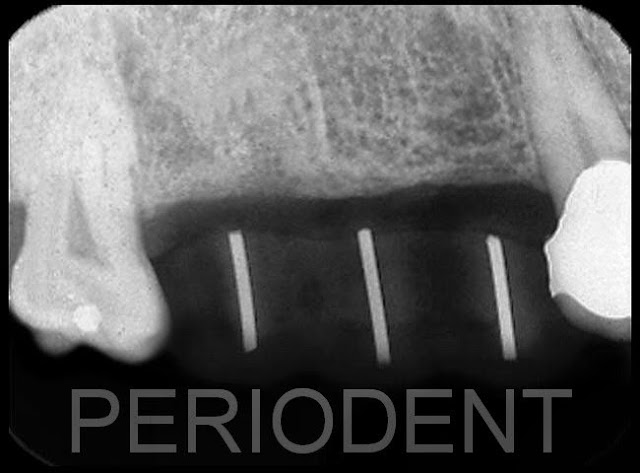

患者決定以植牙重建

植牙第一階段時